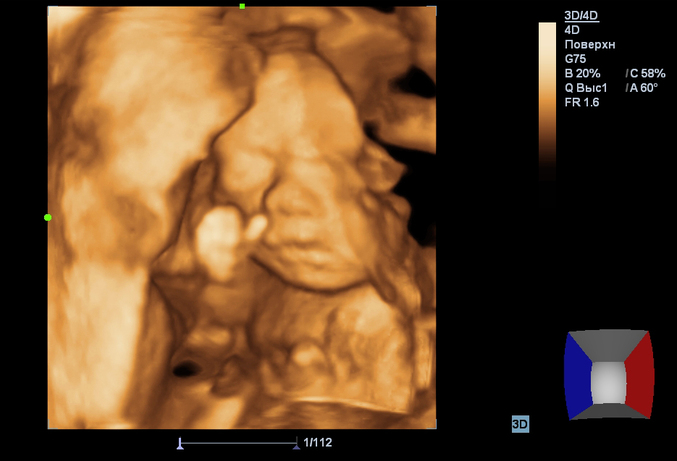

Сделали 4 Д!!!

беременность №2Малышка пряталась, закрывая личико ножками. Но после нескольких манипуляций с животом удалось-таки поймать несколько кадров ) Все у нас в норме и соответствует сроку.

Окружность головки - 216 мм.

Длина плечевой кости - 39 мм.

Длина бедренной кости - 42 мм.

Окружность живота - 190мм.

Плацента: локализация по задней стенке. Толщина - 26мм. Степень зрелости - 0.

Теперь хочется накупить ей целый ворох одежки!!! Прям аж распирает, хоть в магазин беги ))) Сомнений нет - у нас девочка!